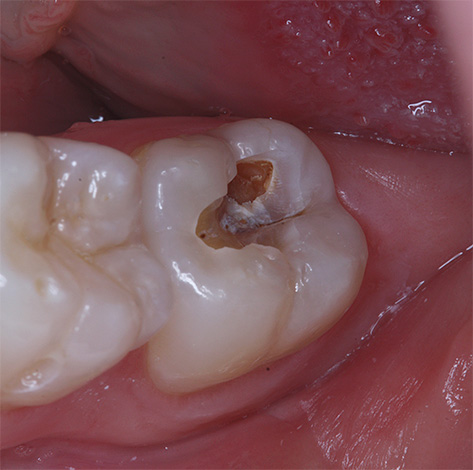

Perguntas sobre as causas, intensidade e duração da dor durante e após o tratamento da cárie são talvez um dos primeiros lugares entre as perguntas populares do dentista-terapeuta. O tratamento de cárie profunda é geralmente a manipulação mais difícil no tratamento de outras lesões de cárie; portanto, infelizmente, nem sempre é sem dor aqui.

O último estágio do desenvolvimento do processo carioso envolve a proximidade de tecidos dentários danificados e infectados a uma polpa saudável ("nervo"). Como resultado disso, sempre existe o risco de confusão entre cáries profundas e o aparecimento de complicações na polpa de um dente quando uma infecção cariada entra nele. Portanto, nesses casos, o tratamento deve ser realizado somente após um diagnóstico detalhado da etapa do processo.